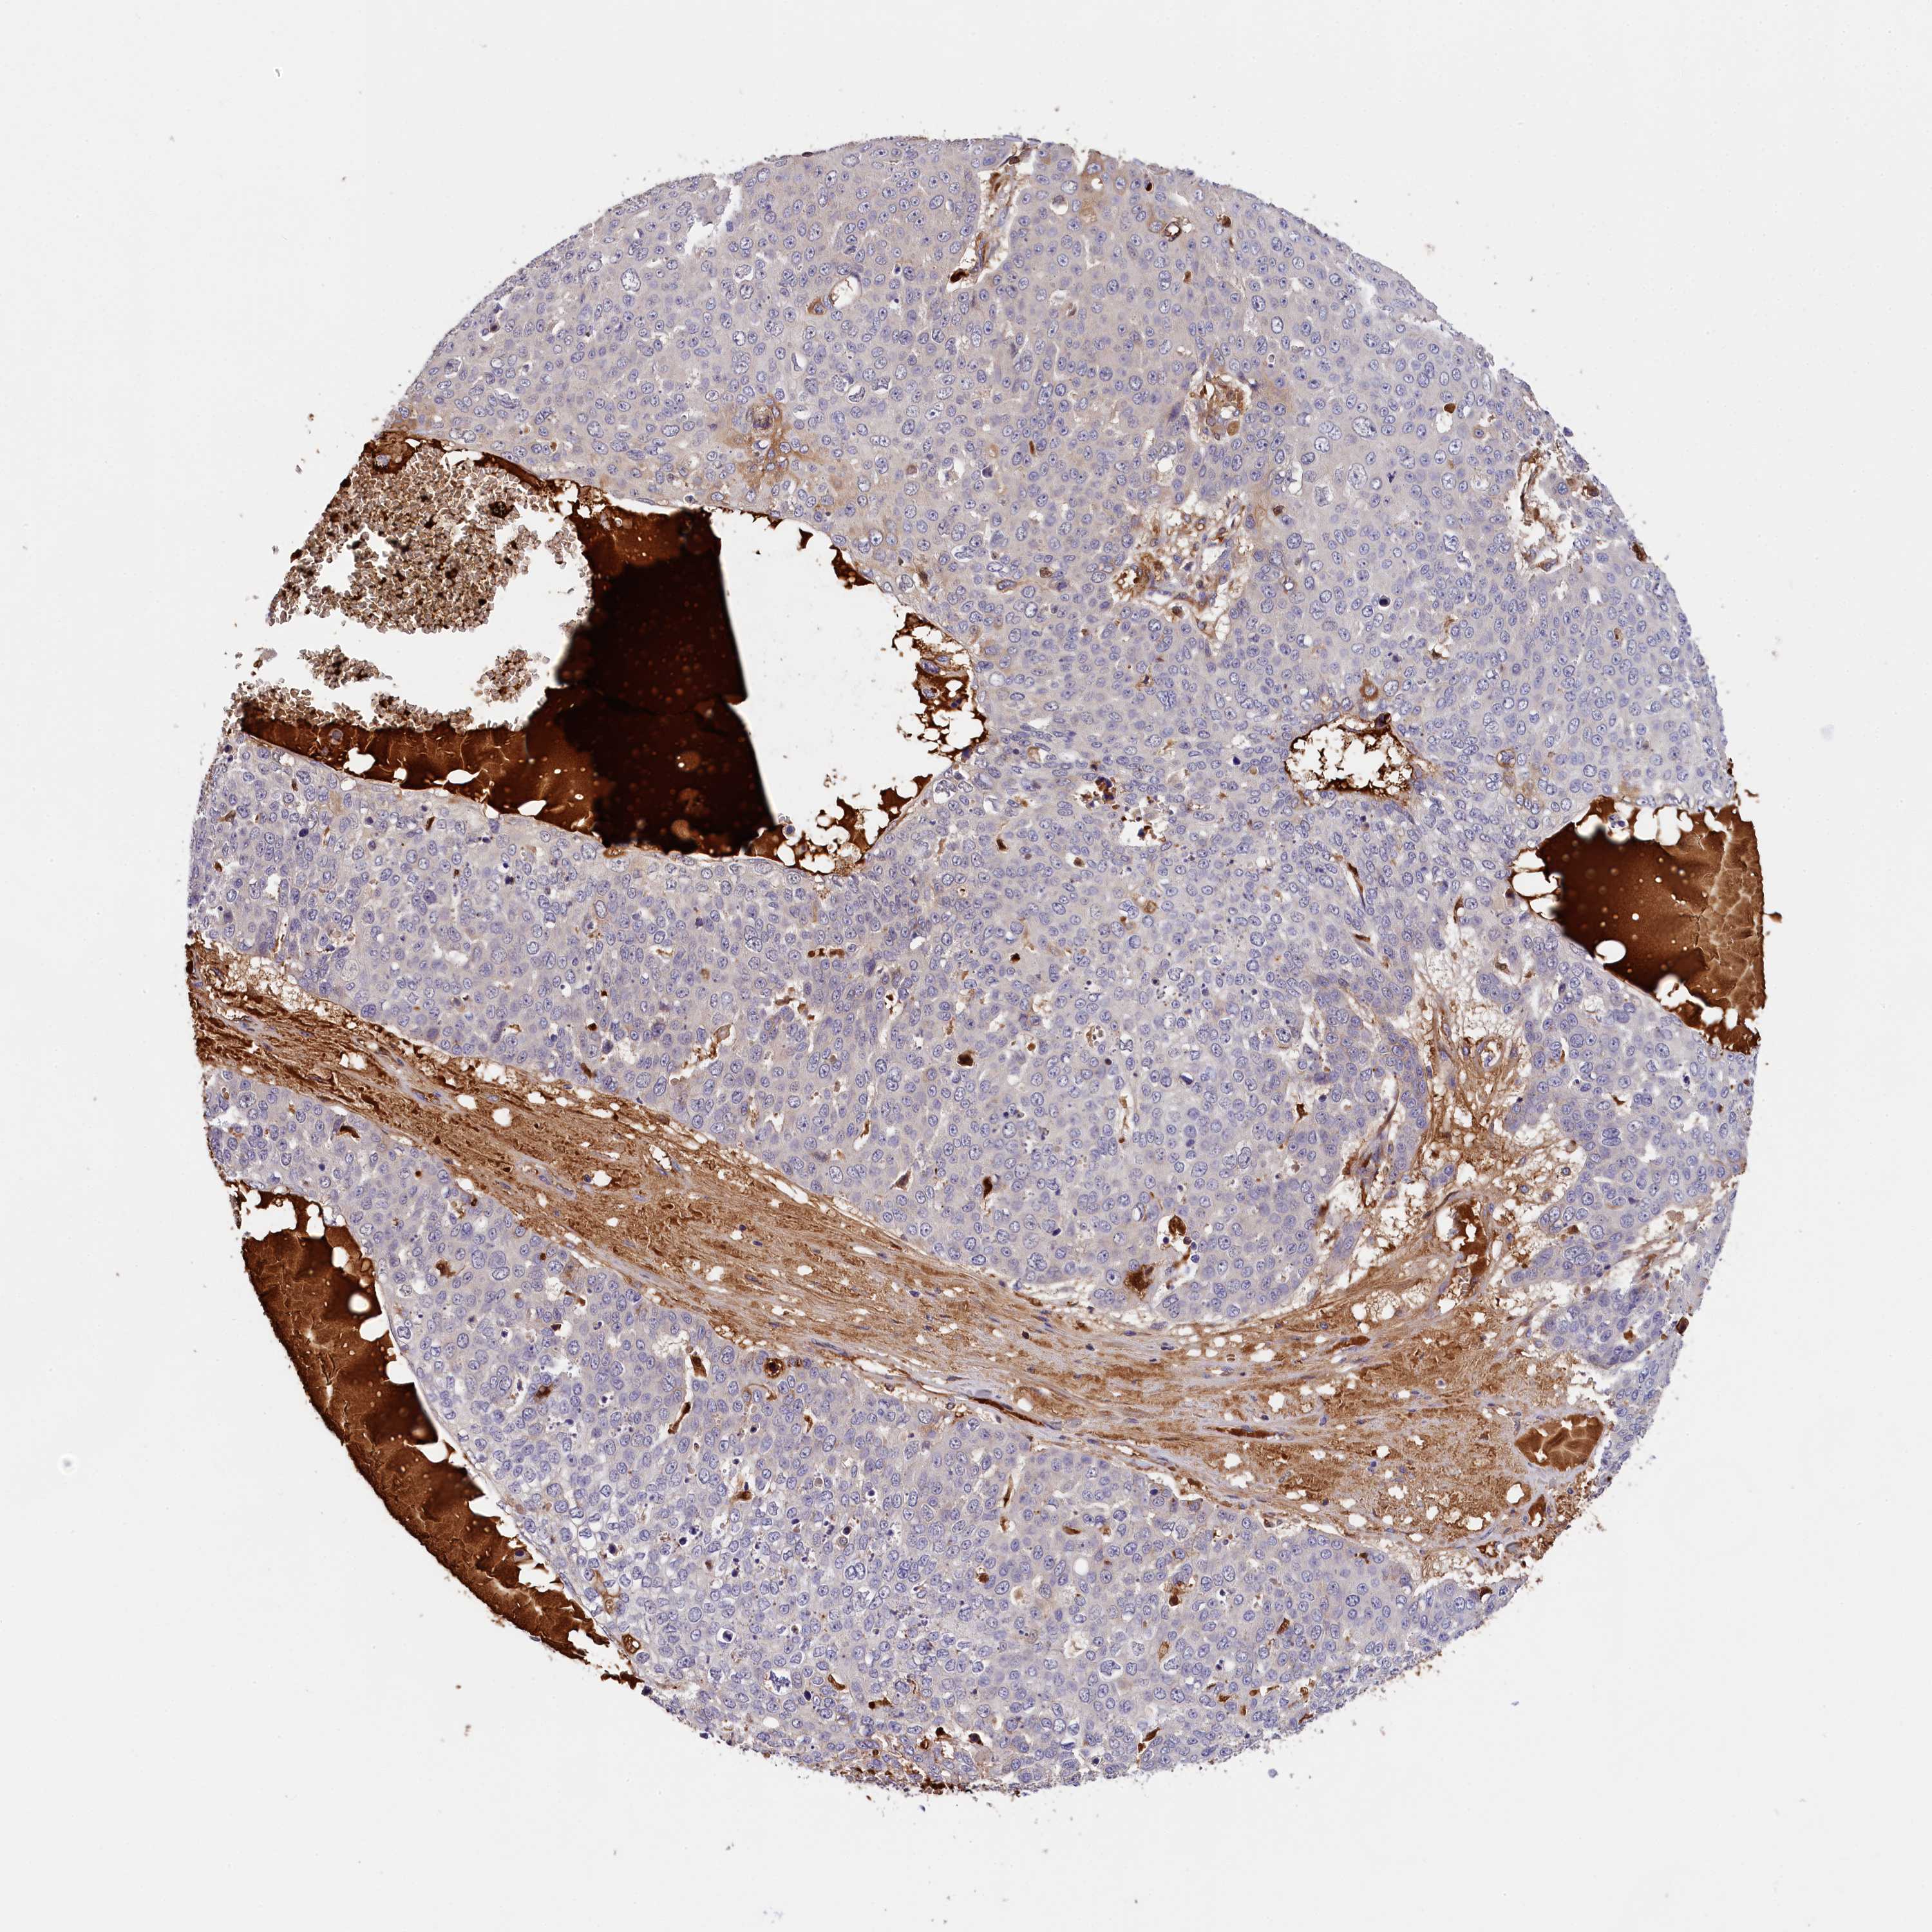

SKIN CANCER - Protein expressioni

A mouse-over function shows sample information and annotation data. Click on an image to view it in a full screen mode. Samples can be filtered based on level of antibody staining by selecting one or several of the following categories: high, medium, low and not detected. The assay and annotation is described here.

Antibody stainingi

Antibody staining in the annotated cell types in the current human tissue is reported as not detected, low, medium, or high, based on conventional immunohistochemistry profiling in selected tissues. This score is based on the combination of the staining intensity and fraction of stained cells.

Each image is clickable and will lead to virtual microscopy that enables deeper exploration of all samples and also displays staining intensity scores, fraction scores and subcellular localization as well as patient and tissue information for each sample.

Antibody HPA041131

Antibody HPA041214

Basal cell carcinoma

Squamous cell carcinoma, NOS

Squamous cell carcinoma, metastatic, NOS